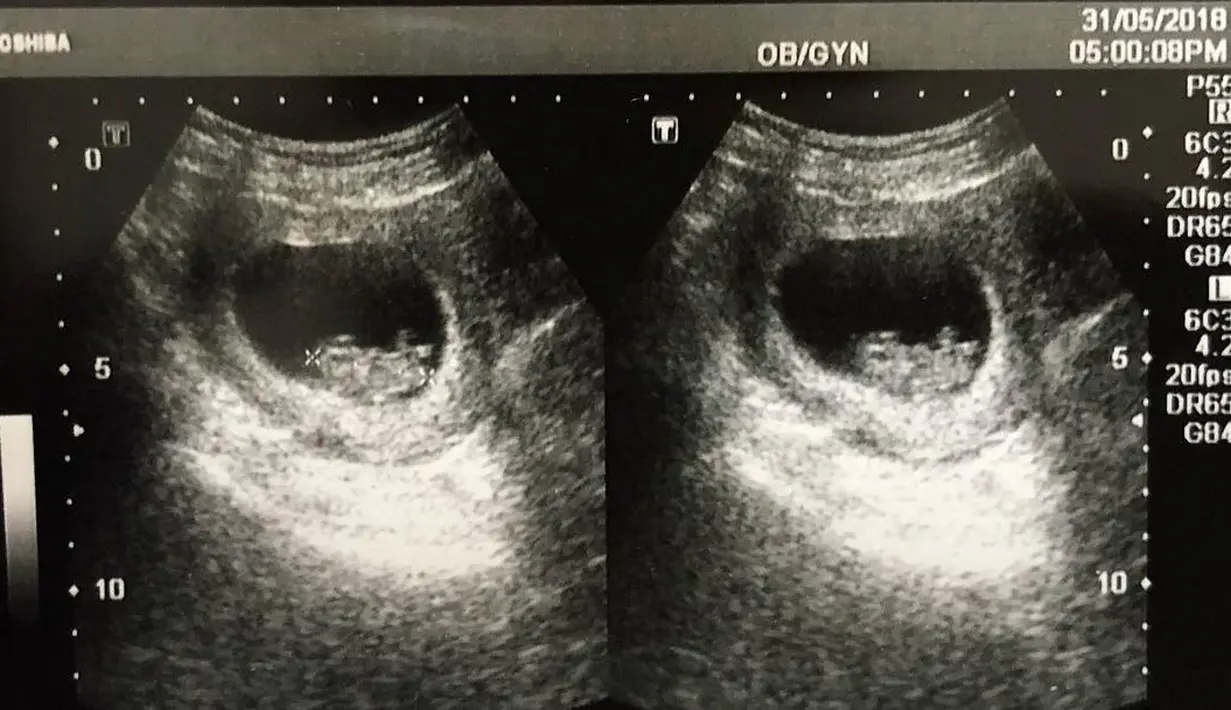

Kabar ini diketahui dari Desta yang mengunggah foto hasil ultrasonography (USG) pada bulan Mei 2018 lalu. Di unggahannya, Desta menuliskan “Yak.. calon penghuni baru kartu keluarga”. (Instagram/desta80s)

Terbaru, Desta kembali membagikan kabar bahagia dengan mengunggah kembali foto hasil USG. Bahagia bukan main, pasalnya anak ketiganya ini berjenis kelamin laki-laki. Mengingat dua anak sebelumnya berjenis kelamin perempuan. (Instagram/desta80s)

"Thank God, Finally It's a BOY" tulis Desta yang sebentar lagi akan menjadi ayah tiga anak. Seperti diketahui,dua gadis ciliknya kini berusia dua dan empat tahun. (Instagram/desta80s)